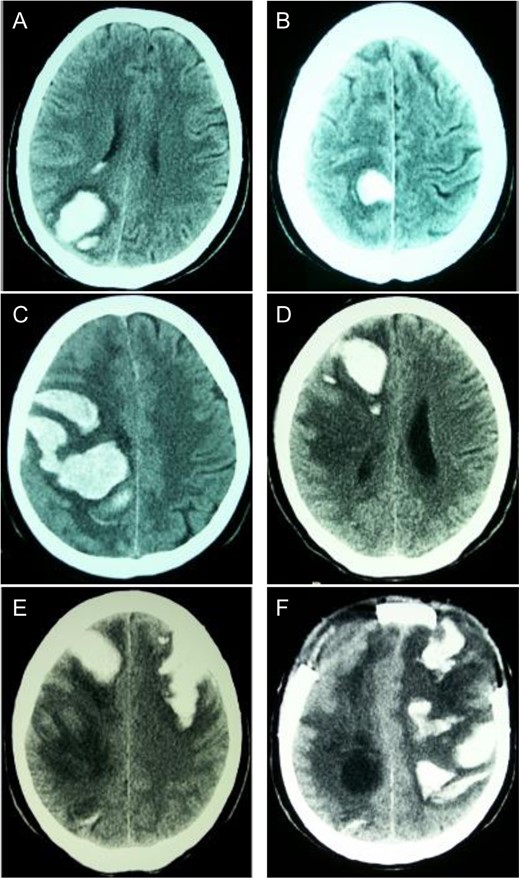

Sequential CT head scans. (A) 3.5 cm ICH in right parieto-occipital lobe with peripheral rim of edema and intraventricular extension; (B) 2.5 cm ICH anterior to first bleed with small ring of surrounding edema; (C) 7 × 4 cm right fronto-parietal ICH with intraventricular extension and subfalcine herniation; (D) 2 × 4 cm ICH in right frontal lobe with surrounding halo of edema and 8 mm subfalcine herniation; (E) 5 × 3 cm left anterior frontal lobe ICH with mild surrounding edema; (F) left fronto-parietal ICH with 2 cm midline-shift.

First ICH: Blood pressure (BP) was 145/75 on admission. Neurological exam revealed left homonymous hemianopsia. She denied any history of trauma, and ensured compliance with her anti-hypertensive medications. Computed tomography (CT) scan of her head revealed an ICH in the right parieto-occipital region (Fig. 1A). Routine coagulation parameters (INR, PTT and platelets) were unremarkable. Cerebral angiogram was performed and revealed no evidence of a vascular abnormality. The patient was discharged home with a resolving left homonymous hemianopsia. A follow-up CT revealed an evolving ICH.

Second ICH: Five weeks after initial presentation the patient returned with a spontaneous onset of mild left leg weakness. Repeat CT revealed a new ICH anterior to the initial ICH, though the patient was neurologically stable (Fig. 1B).

Third ICH: Six weeks after initial presentation, the patient awoke with left sided hemiparesis, facial drooping and severe headache. Progressive decreased level of consciousness led to intubation in the ER and CT scan showed new ICH in the right fronto-parietal area (Fig. 1C). On examination, BP was 135/76, brainstem reflexes were intact and the patient localized only with her right upper extremity. Decerebrate posturing on the left side was demonstrated with brisk deep tendon reflexes and a positive left Babinski response. Routine hematological investigations were unremarkable. Urgent decompressive craniotomy was performed for evacuation of ICH.

Fourth ICH: Three weeks later, while in the Step-down Unit, the patient experienced another ICH localized in the anterior right frontal lobe (Fig. 1D).

Fifth ICH: Six days later, the patient experienced a sudden decreased level of consciousness with two generalized seizures. Repeat CT scan revealed a new ICH in the left anterior frontal lobe (Fig. 1D). Urgent craniotomy was performed with evacuation of bi-frontal hematomas and a brain biopsy specimen was sent for pathology analysis. Histopathological examination demonstrated no evidence of vascular malformation or neoplastic process. However, immunohistochemistry and Congo red staining (previously described [3]) confirmed beta-amyloid deposition in cortical and leptomeningeal vessel walls, and the adjacent brain parenchyma presented neuritic Alzheimer-type plaques (Fig. 2). Finally, blood specimen analysis via polymerase chain reaction/restrictive fragment length polymorphism revealed an ApoE genotype Є2/Є3.

Sixth ICH: Two weeks later, the patient’s neurological status deteriorated significantly and CT revealed a new left fronto-parietal ICH (Fig. 1F). In view of the likelihood of poor quality of life, a decision was made with the family to withdraw active care and the patient passed away shortly thereafter.